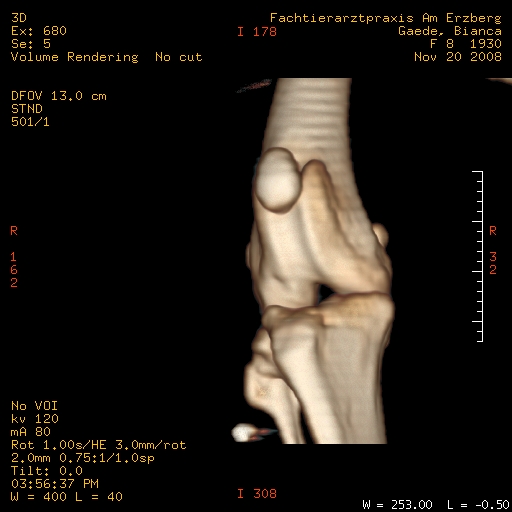

Im CT mit Kontrastmittel hat man den Riss nicht sehen können, nur die Flüssigkeitsansammlung im Knie.Persönlich, wenn es unklar ist, sprich auch der Schubladentest negativ ist, würde ich wohl eher ein MRT machen lassen, wenn die Möglichkeit besteht.

Ich finde, so wirklich erkennen kann man nicht, daß das Kreuzband gerissen ist. Klar, die Arthrose kann man sehen und mehr Flüssigkeit, aber sonst